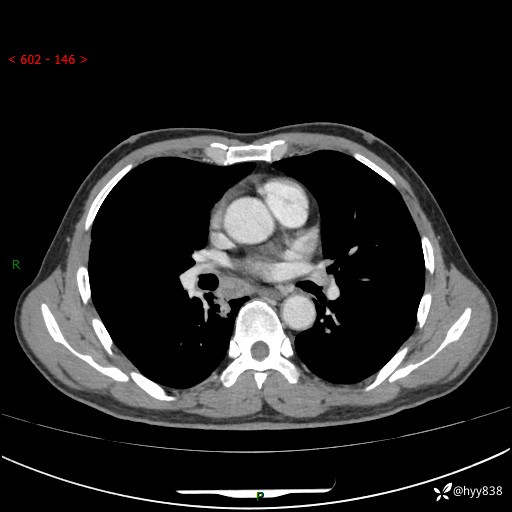

69岁/男,发现肺部病变6天。该有的征象都有,肉芽肿 VS 肿瘤,一念之间---(有结果)

主诉:发现肺部病变6天。

现病史:患者6天前于我院泌尿外科住院,住院期间行胸部CT检查,提示“肺部病变”,患者无畏寒、发热、盗汗、咳嗽、咳痰、咯血、胸痛、呼吸困难,无反酸、腹痛、腹泻、头痛、头晕等不适。未予特殊处理,现为进一步诊治,门诊以“肺肿物”收入我科。 患者本次起病以来,精神食欲尚可,大小便正常,体力及体重无明显变化。

胸部CT平扫+增强